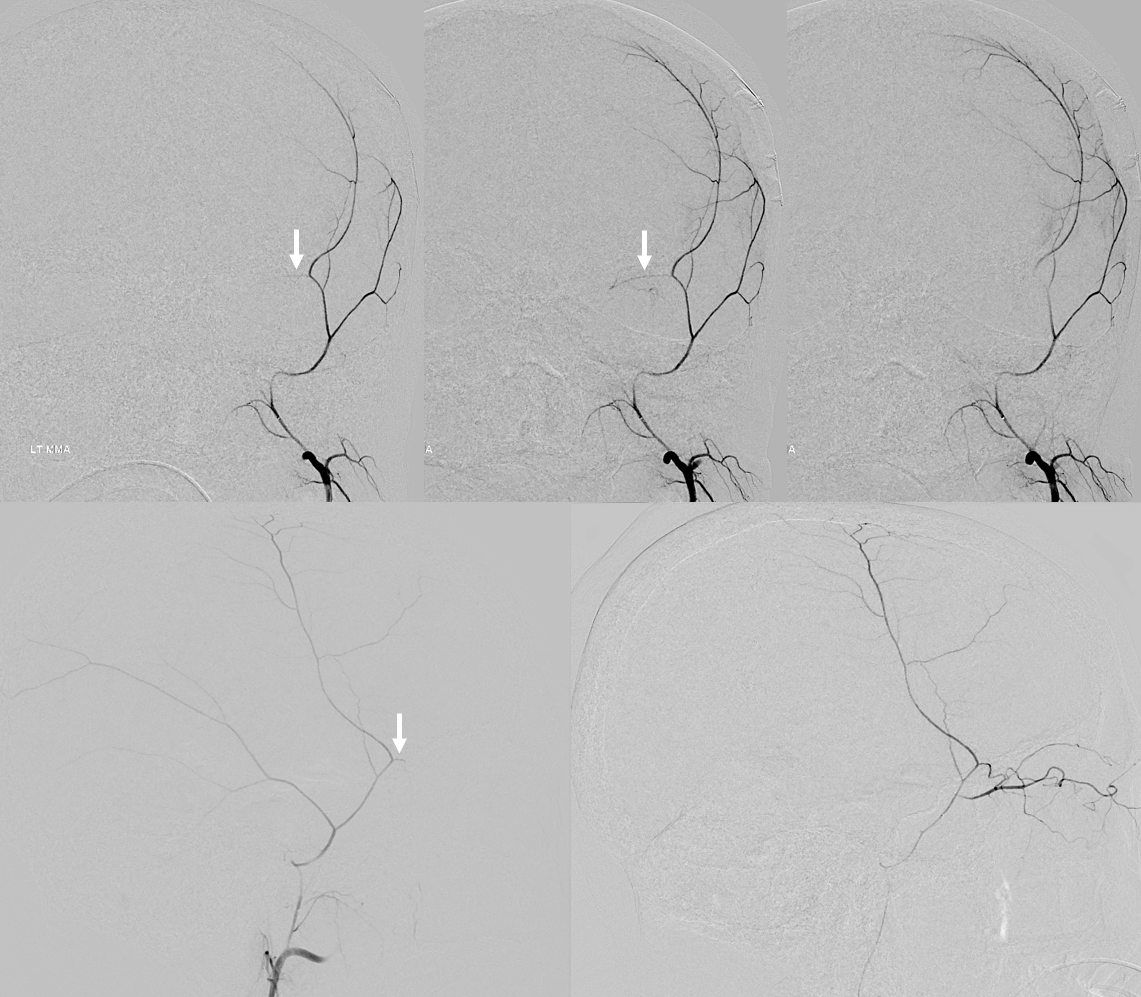

Below is a representative arteriovenous injection sequence, frontal and lateral views, in a patient presenting for MMA embo for subdural hematoma. The catheter is located in the frontoparietal division. Notice connection with the anterior meningeal/SSS frontal branch (white arrows), the characteristic tramtrack appearance of the middle meningeal vein (dashed arrows) and additional drainage of the meninges likely via an emissary vein towards the deep temporal space (open arrows). Not all meninges drain into the middle meningeal veins — some do, while others find other routes. Notice the characteristic hypervascularity of the meninges in the subdural hematoma state. The double=mask technique in the right lower lateral image superimposes white arterial phase on the dark venous phase.

Same image, now arrows

Same patient, with catheter in the petrosquamosal branch. Here, contrast extends transiently towards the midline of the proximal superior sagittal sinus branch (black arrow). Venous phase shows drainage of the dural into the sigmoid sinus.Â

Unsubtracted views. Distal tip is solid arrow, proximal dashed arrow. Notice that despite “proximal” appearance of the distal tip in the lateral view (apparently not yet beyond the expected location of the facial nerve arcade / stylomastoid foramen), the frontal view shows that the distal tip is quite lateral, well beyond origin of the “dangerous” petrous branch — which typically comes off very proximally, very soon after MMA emerges from spinosum. The frontoparietal branch has already been embolized with particles and closed with a coil. Notice post-embolization contrast stasis in the subdural collection, outlined by the oval.Â